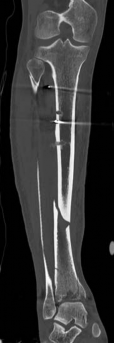

Pre-operative planning is the cornerstone of successful execution in complex pilon-variant tibial shaft fractures. The surgeon must transition from a conceptual understanding of the injury to a concrete, step-by-step surgical blueprint. This begins with high-quality orthogonal radiographs of the entire tibia, ankle, and knee. However, plain films drastically underestimate the degree of articular comminution and central impaction. A fine-cut computed tomography (CT) scan with 2D multiplanar reformats (coronal and sagittal) and 3D surface rendering is absolutely mandatory.

The CT scan allows the surgeon to map the fracture lines, identify the primary articular fragments (Chaput, Volkmann, medial malleolus), and quantify the degree of central die-punch impaction. In an AO/OTA 43C3.3 fracture, where no articular fragment is in continuity with the diaphysis, the surgeon must plan the sequence of reduction. Typically, the fibula is addressed first to restore lateral column length and rotation, provided the fibular fracture is not located at the level of the syndesmosis where fixation might interfere with the lateral surgical approach to the tibia.